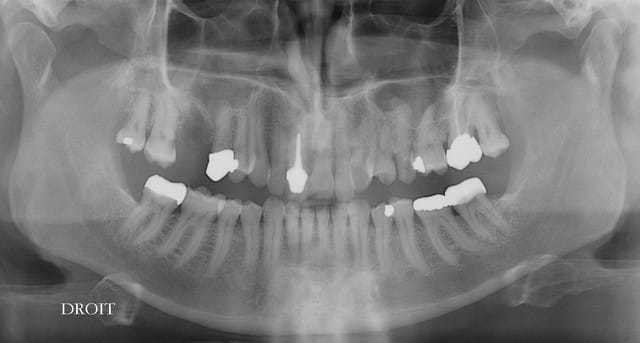

extract récente implant + Vitalos

moi, ce qui m'interpelle, c'est le choix de l'EEI qui t'oblige à te laisser embarquer dans une alvéole qui ne te donnera pas forcement le meilleur axe ni le meilleur centrage

pourquoi ce choix?

> moi, ce qui m'interpelle, c'est le choix de l'EEI qui t'oblige à te laisser

> embarquer dans une alvéole qui ne te donnera pas forcement le meilleur axe ni le

> meilleur centrage

> pourquoi ce choix?

pas forcément l'os où je voulais